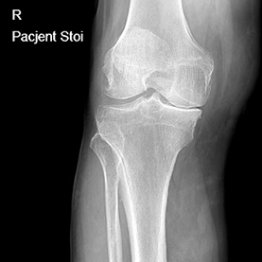

Endoproteza stawu kolanowego

Endoprotezoplastyka stawu kolanowego to skuteczna metoda leczenia zaawansowanej choroby zwyrodnieniowej kolana. Zabieg polega na chirurgicznym usunięciu uszkodzonych powierzchni stawowych i ich zastąpieniu nowoczesnym implantem – całkowitym lub częściowym – który przywraca funkcję stawu, poprawia jego stabilność i eliminuje ból. Leczenie to jest przeznaczone dla pacjentów z silnymi dolegliwościami bólowymi, ograniczeniem ruchomości, sztywnością kolana oraz brakiem efektów leczenia zachowawczego.

Dobór rodzaju implantu zależy od stopnia zaawansowania zmian zwyrodnieniowych i oczekiwań pacjenta. Wszystkie zabiegi przeprowadzam w oparciu o zasady protokołu fast-track surgery – nowoczesnego podejścia, które minimalizuje czas hospitalizacji, przyspiesza rozpoczęcie rehabilitacji i poprawia ogólne wyniki leczenia.